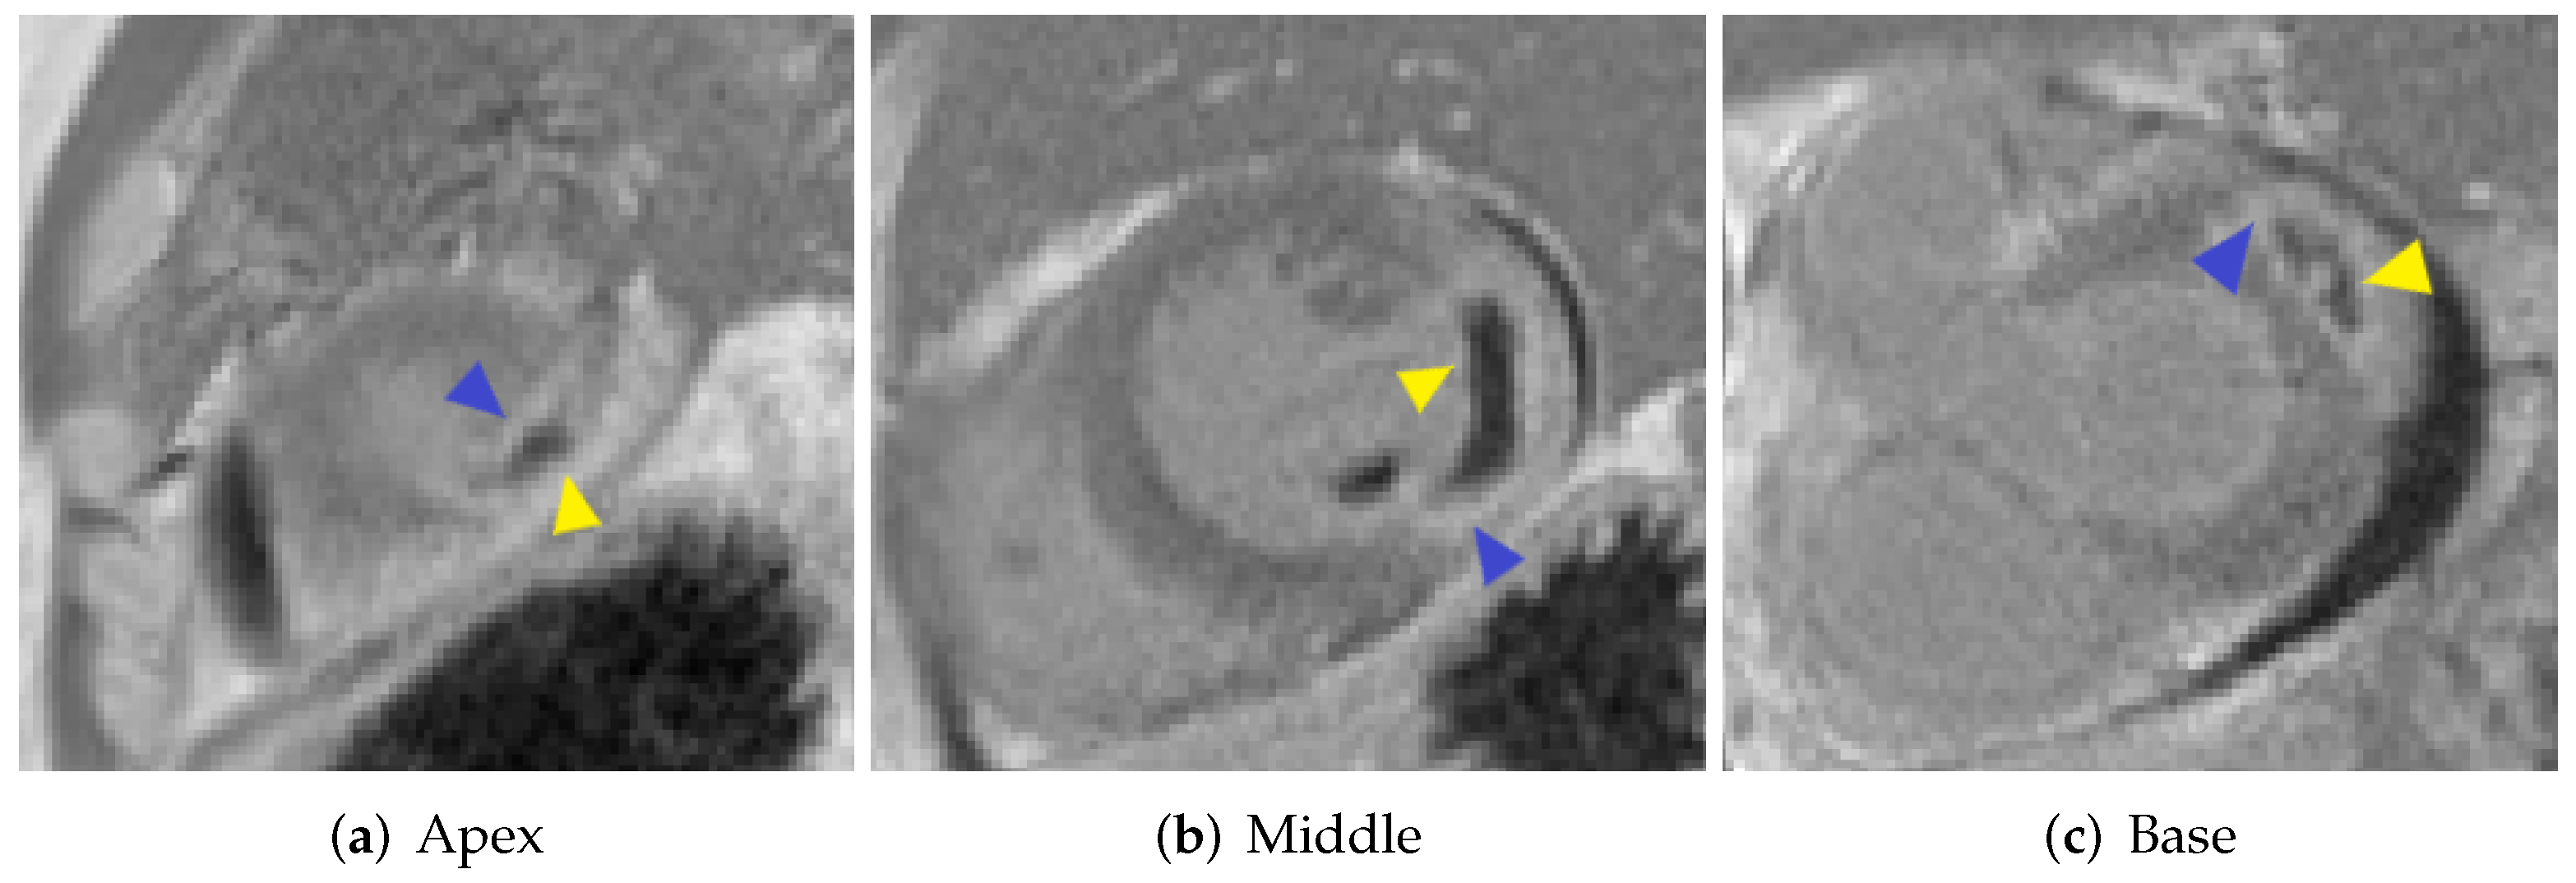

Figure 1 shows short-axis LGE-MRI at the base, middle, and apical ventricular levels, illustrating a large region of hyperenhancement (scar) with a hypo-enhanced central area (MVO).

Figure 1. Short-axis LGE-MR images show MI (blue triangular) and MVO (yellow triangular).